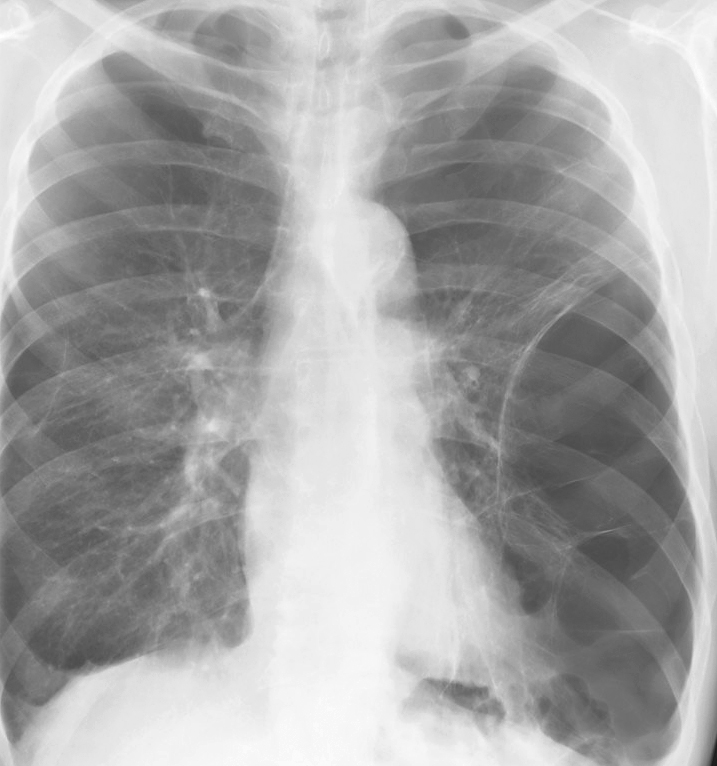

Gallery COPD bulla LLL

bulla LLL